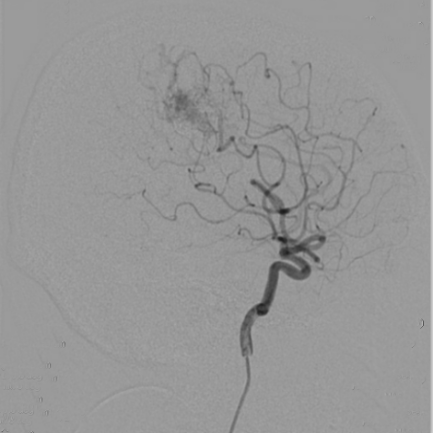

病例名称:颅内动静脉畸形的介入治疗 病史: 男性,62岁 主因“间断头疼半天”入院。 曝光模式及参数: DSA,减影3D 造影表现: DSA造影,造影提示右颈内动脉有巨大畸形血管团

为了观察动静脉畸形的栓塞效果,术后行DSA造影。DSA造影显示畸形团基本消失,栓塞效果较好